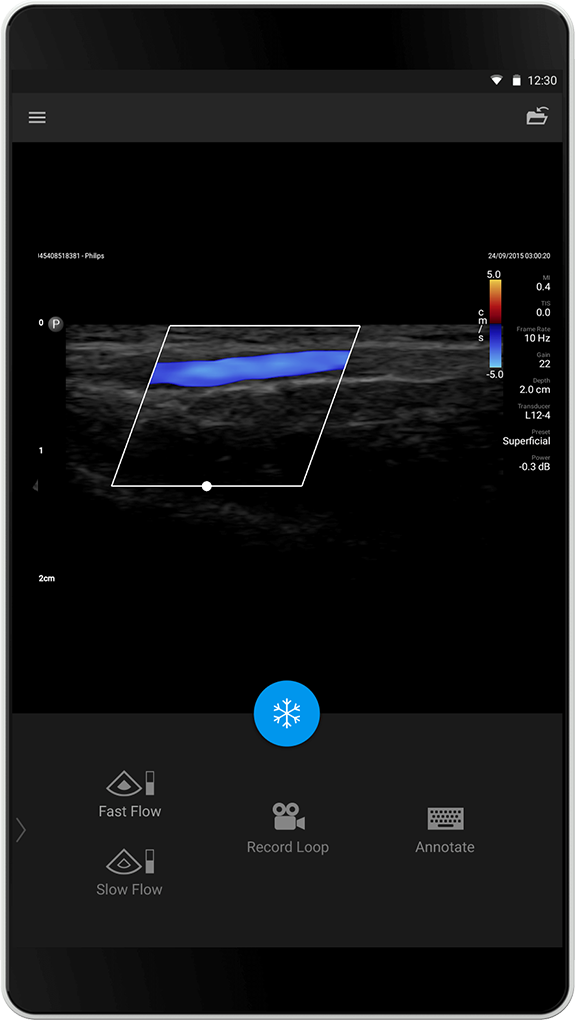

Forhåndsinnstillingen Superficial (Overfladisk) er optimalisert for programmer for overfladisk avbildning med høy oppløsning, for eksempel for å differensiere cyster og fremmedlegemer.